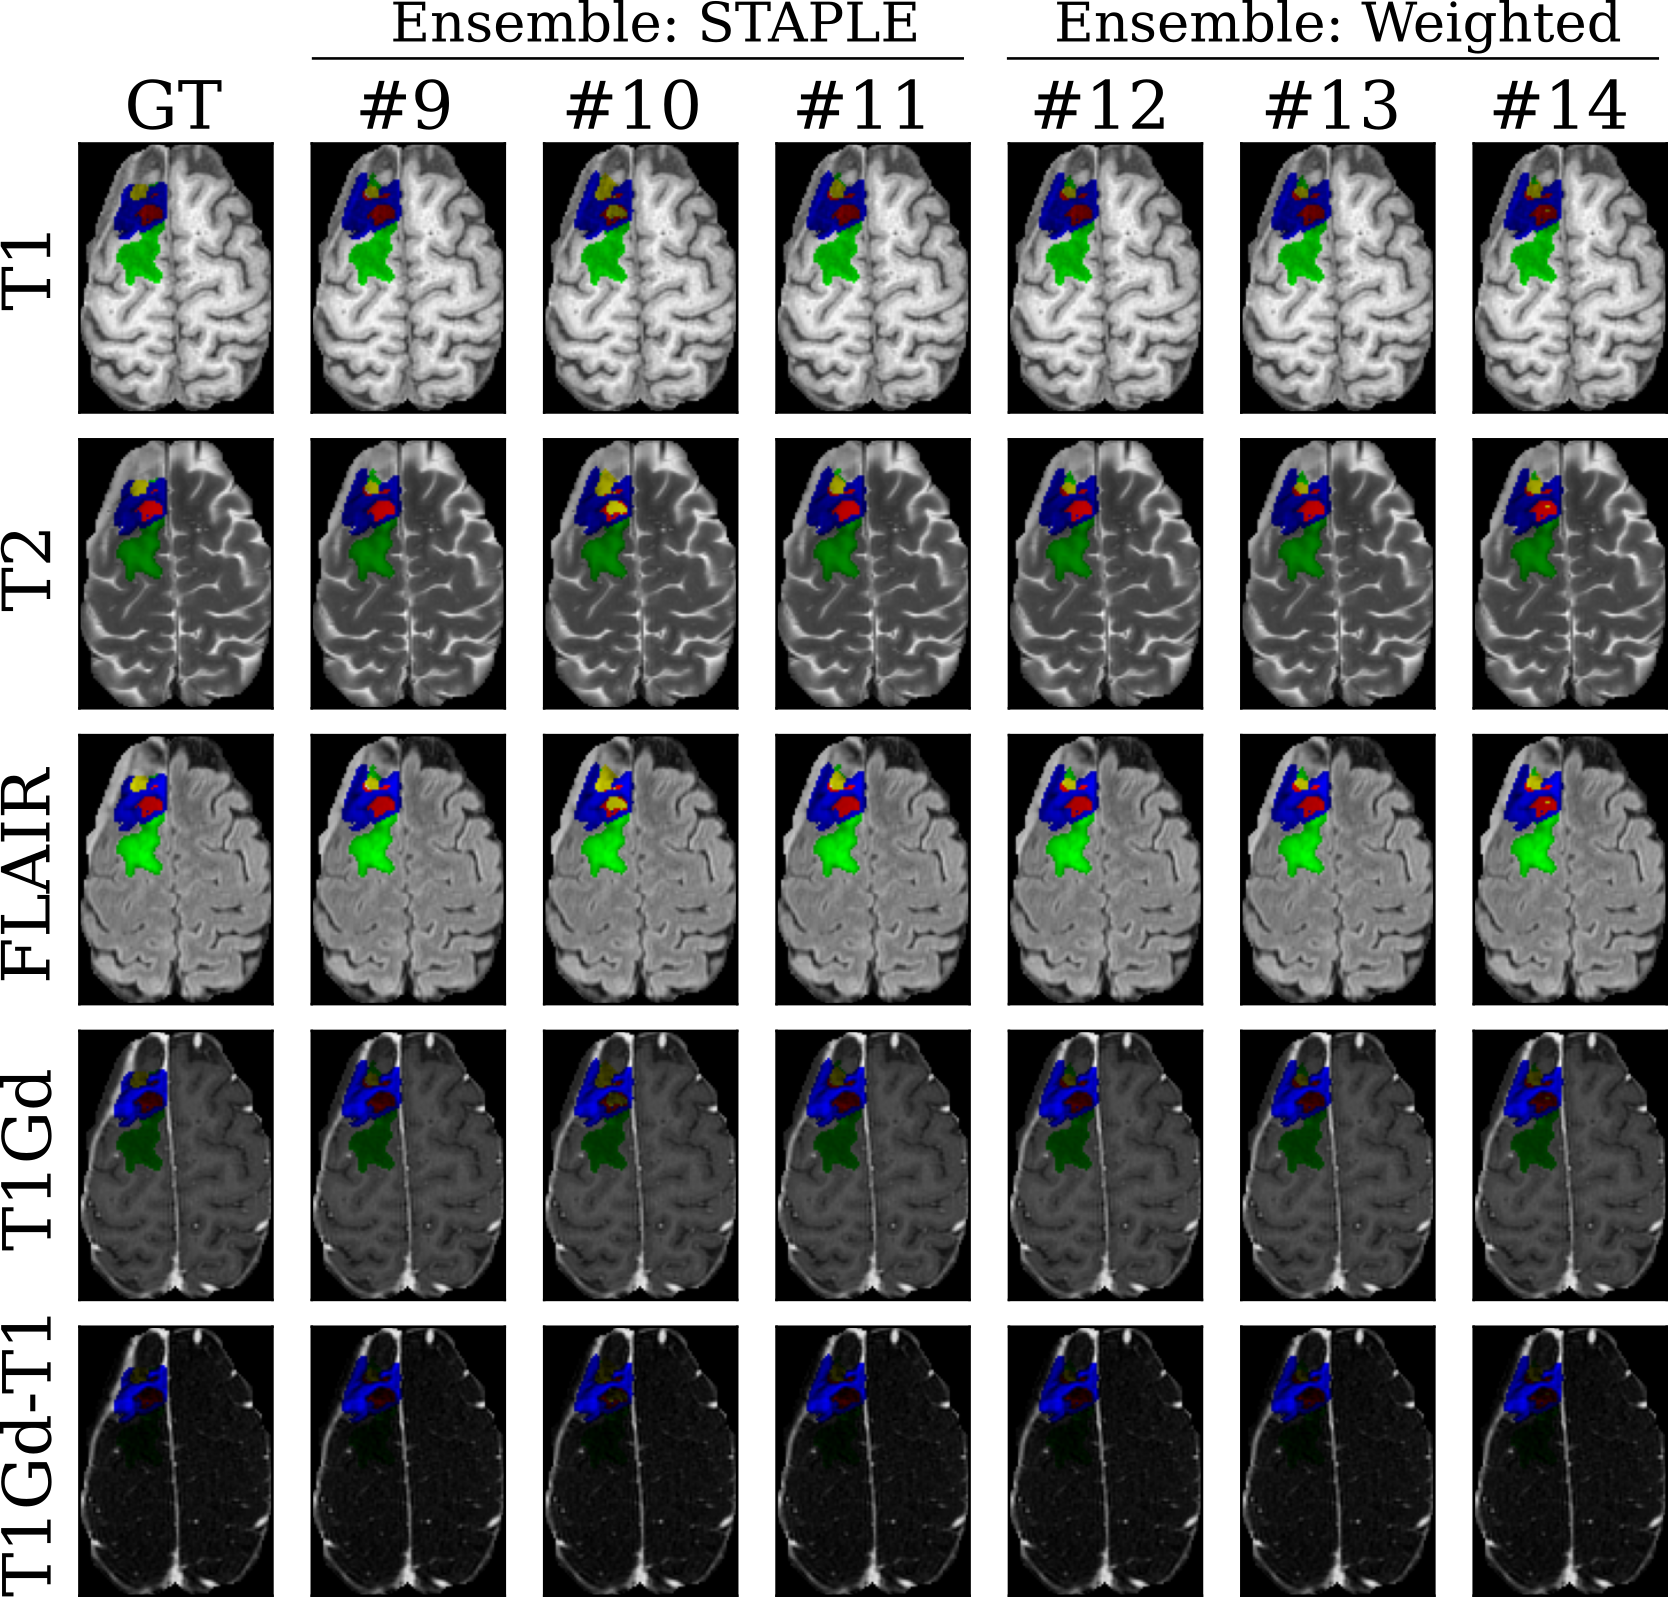

Figure 3: Segmentation results visualization on one subject in the internal validation set on the different MR imaging input modalities (lines). The ground truth annotation (GT) is compared against our ensemble models using STAPLE (columns #9 to #11) and the proposed weighted approach (columns #12 to #14). Labels include enhancing tissue (ET, blue), non-enhancing tumor core (NETC, red), surrounding non-enhancing FLAIR hyperintensity (SNFH, green), and resection cavity (RC, yellow).

For the internal validation set, we show results for LD and LH95 scores in Table 1 and Table 2. For index #1-4, we calculate LD and LH95 for each baseline with 4 input scans. For index #5-9, we calculate LD and LH95 with 5 input scans, including the additional T1Gd-T1 input scan. Figure 2 presents qualitative segmentation results for one subject in the internal validation set for the baseline models with (columns #1-4) and without (columns #5-8) including the additional T1Gd-T1 input scan against the ground truth annotations (GT). While both groups of models depict similar predictions for the SNFH label (green), we observe more accurate contours for the ET (blue) using the proposed additional input. For indices #9-11 and #12-14, we calculate STAPLE/weighted ensemble results with respect to the aforementioned baselines. We observe that for single baseline results, incorporating additional channel input generally improves LD scores. We also observe better LD and LH95 scores with larger baseline models (ResEncUNetL to ResEncUNetXL). For ensemble approaches, STAPLE and weighted average generally improve performance compared with single baselines. In Figure 3, we visualize qualitative segmentation results for one subject in the internal validation set for ensemble models using STABLE (columns #9-11) and the proposed weighted approach (columns #12-14) against the ground truth annotations (GT). For the selected subject, the STABLE ensemble models provide a better detection of the RC (yellow) while the proposed weighted ensemble models focus on accurate segmentation of the NETC (red).